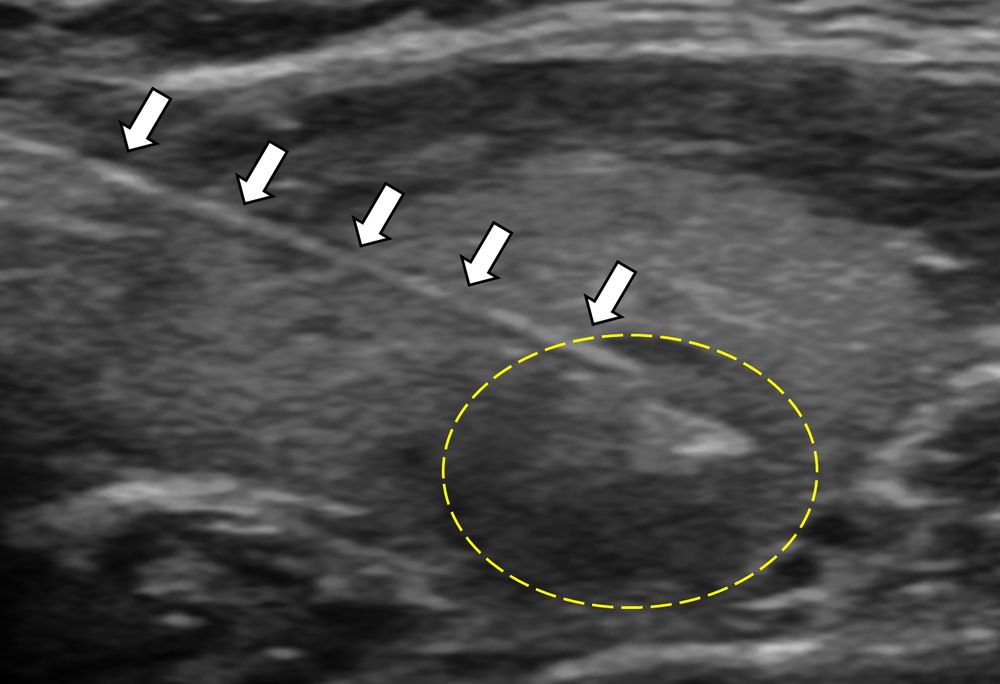

Η διαδερμική βιοψία είναι μία ελάχιστα επεμβατική μέθοδος λήψης υλικού από τον όγκο για κυτταρολογική και ιστολογική εξέταση, από εστιακές αλλοιώσεις του ήπατος, πνεύμονα, νεφρού κλπ. Συστήνεται από τον κλινικό ιατρό ανάλογα με το είδος και το μέγεθος της βλάβης και πραγματοποιείται με ασφάλεια από επεμβατικό ακτινολόγο με την καθοδήγηση αξονικού τομογράφου ή υπερήχων. Στη σύγχρονη ογκολογική θεραπεία όπου γίνεται προσπάθεια καταπολέμησης του καρκίνου σε μοριακό επίπεδο κρίνεται αναγκαία η ακριβής ιστολογική ταυτοποίηση του όγκου ώστε να εφαρμοσθεί εξατομικευμένη θεραπεία για το βέλτιστο αποτέλεσμα. Οι κατευθυνόμενες βιοψίες στοχευουν στο να παρέχουν στον κλινικό ογκολόγο το απαραίτο ιστοπαθολογικό υλικό που θα του επιτρέψει να εφαρμόσει την κατάλληλη θεραπεία για τον ογκολογικό ασθενή.